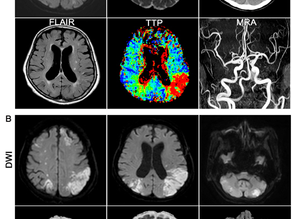

Chemical and perfusion markers as predictors of moyamoya disease progression and complication types. Sci Rep 2024 [교신저자]

Jae Hyun Kim # 1 , Hanwool Jeon # 1 2 3 4 , Moinay Kim 1 , Joonho Byun 5 , Yeongu Chung 6 , Si Un Lee 7 , ...